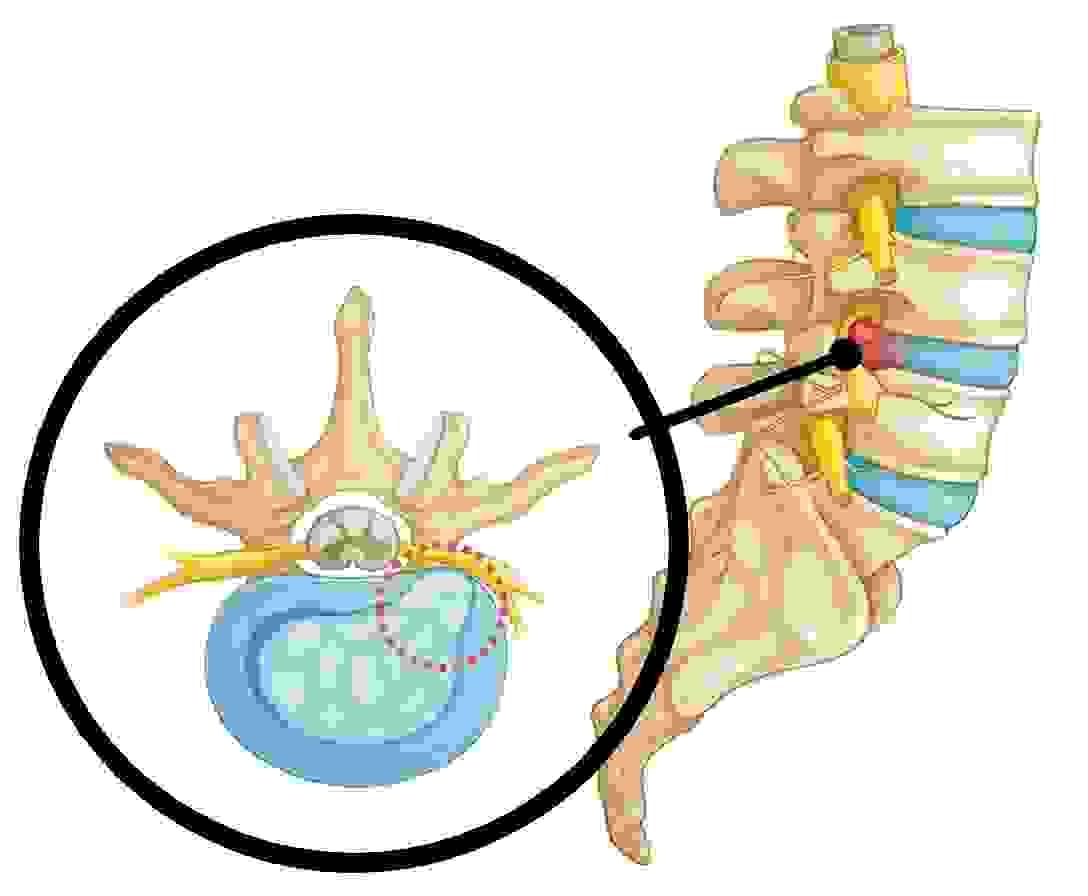

神經線介紹

頸椎有7節, 胸椎有12節, 腰椎有5節......

如有脊椎錯位或椎間盤突出, 就有機會壓迫神經線, 令一些症狀出現!